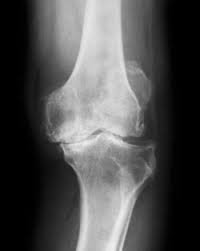

تشخيص خشونة الركبة بدقة

يعتمد التشخيص لدى دكتور هشام عبد الباقي على:

- الفحص الإكلينيكي الدقيق

- الأشعة السينية لتحديد درجة التآكل

- الرنين المغناطيسي لتقييم الغضروف والأنسجة المحيطة

التشخيص الدقيق هو حجر الأساس لاختيار علاج تآكل غضروف الركبة المناسب.

الدرجة الرابعة

- ألم شديد حتى أثناء الراحة

- فقدان كبير في الحركة

- تشوه في شكل المفصل

- تآكل شبه كامل أو كامل لغضروف الركبة